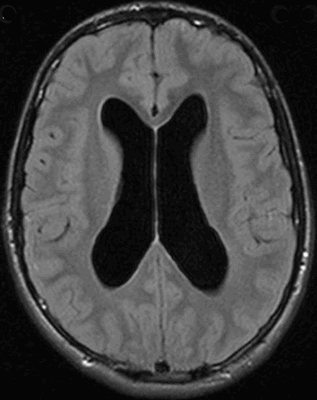

Хроническая несообщающаяся обструктивная гидроцефалия

Хроническая несообщающаяся гидроцефалия (син. хроническая обструктивная гидроцефалия) довольно легкий диагноз. С течением времени желудочковая система выше уровня обструкции постепенно увеличивается, что приводит к сдавлению и истончению коры. Признаки долго текущей несообщающейся обструктивной гидроцефалии (на уровне Сильвиевого водопровода) включают 1: